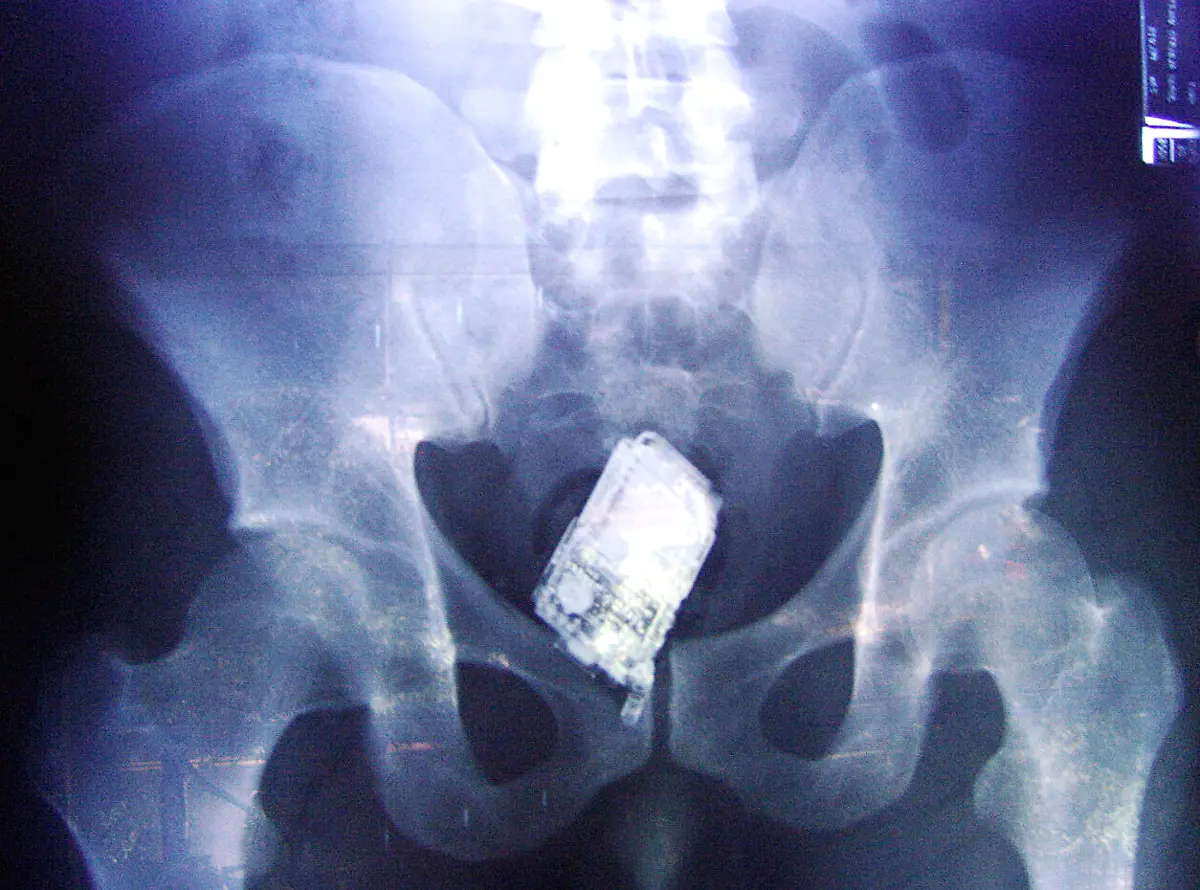

Nägel, Messer, TelefoneWas Röntgenstrahlen zum Vorschein bringen

Nicht immer zeigen Röntgenaufnahmen das, was man von ihnen erwartet. Oft kommt es zu Bildern, die selbst hartgesottene Betrachter zum Schaudern bringen - und der Wissenschaft Rätsel aufgeben.